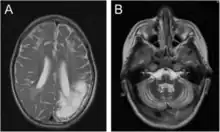

Encéphalomalacie chez un garçon de 7 ans : en imagerie par résonance magnétique (àa gauche) et en tomodensitométrie (à droite)